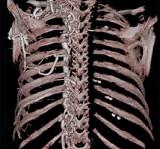

问题 下面一组图像显示的是 ( )

选项 A、奇静脉增粗可见于各种病因引起的上腔静脉梗阻 B、奇静脉增粗可见于各种病因引起的下腔静脉梗阻 C、正常的奇静脉干直径小于1.0cm D、奇静脉弓层面其直径小于1.2cm E、奇静脉扩张

答案 ACDE